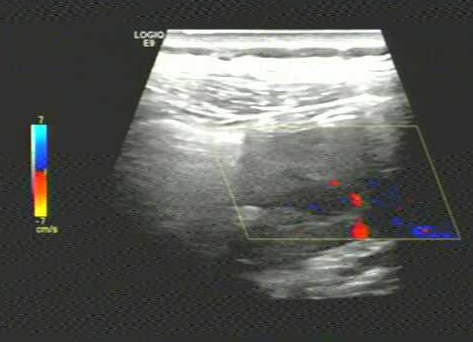

彩色多普勒示低回声团周边及内可见稍丰富血流信号。